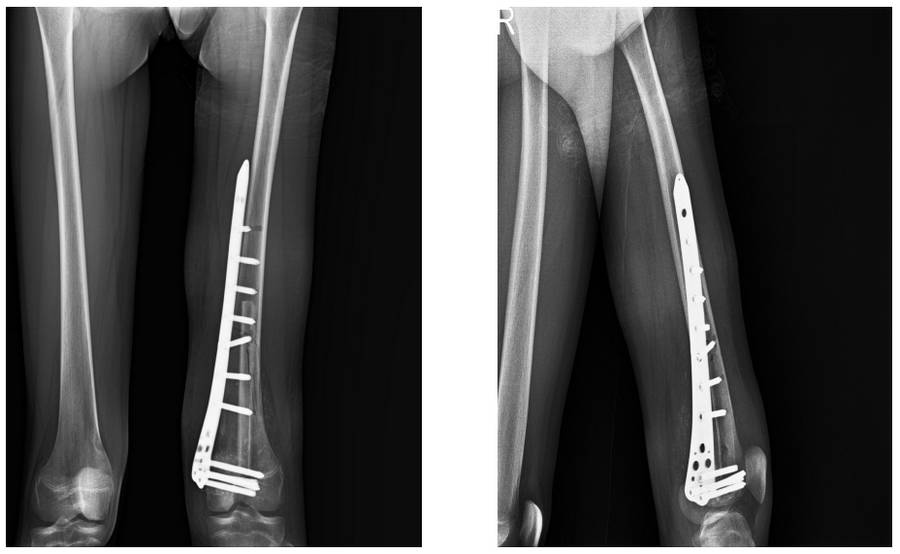

VAKA 15: Diz (Distal Femur) Yerleşimli Osteosarkom

Distal femur medial yerleşimli osteosarkom nedeniyle kemoterapiyi takiben hemikortikal rezeksiyon sonrası sıvı azot ile geri kazanım ve vaskülerize fibula ile kombinasyon uygulanan genç kadın hastamız

Ameliyat Sonrası: Röntgende fibula ile kombine edilmiş geri kazanılmış kemiğin titanyum anatomik plak ile uygulanımı görülmekte